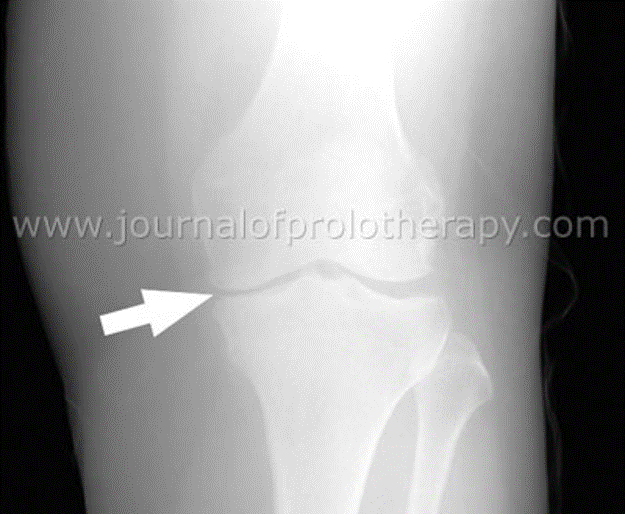

Prolozone treatment helps anything that hurts, including knee pain